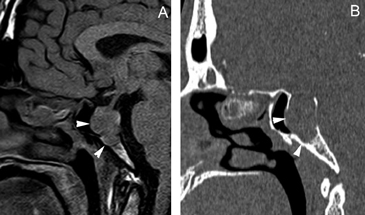

Figura 19A y B. Cortes sagitales T1w antes y después de inyección de Gadolinio. El tumor (prolactinoma) crece hacia caudal, invade el seno esfenoidal y erosiona el clivus (puntas de flecha), dejando libre la cisterna quiasmática. Los adenomas pituitarios invasores tienen características histológicas benignas, los malignos (carcinomas pituitarios) constituyen sólo el 0,2-0,5% de todos los tumores pituitarios50 y generalmente son macroadenomas funcionantes recidivados,que se presentan con metástasis subaracnoideas, cerebrales o sistémicas (Figuras 20 A, 20B, 20C y 20D).

Figura 20A y B. Cortes sagitales, secuencia T1 sin y con Gad. Prolactinoma maligno que invade el seno esfenoidal, el clivus, se extiende a la cisterna supraselar. C y D cortes axiales transversal y coronal, secuencia T1w con Gad. demuestran invasión subaracnoidea y del lóbulo temporal izquierdo (punta de flecha).